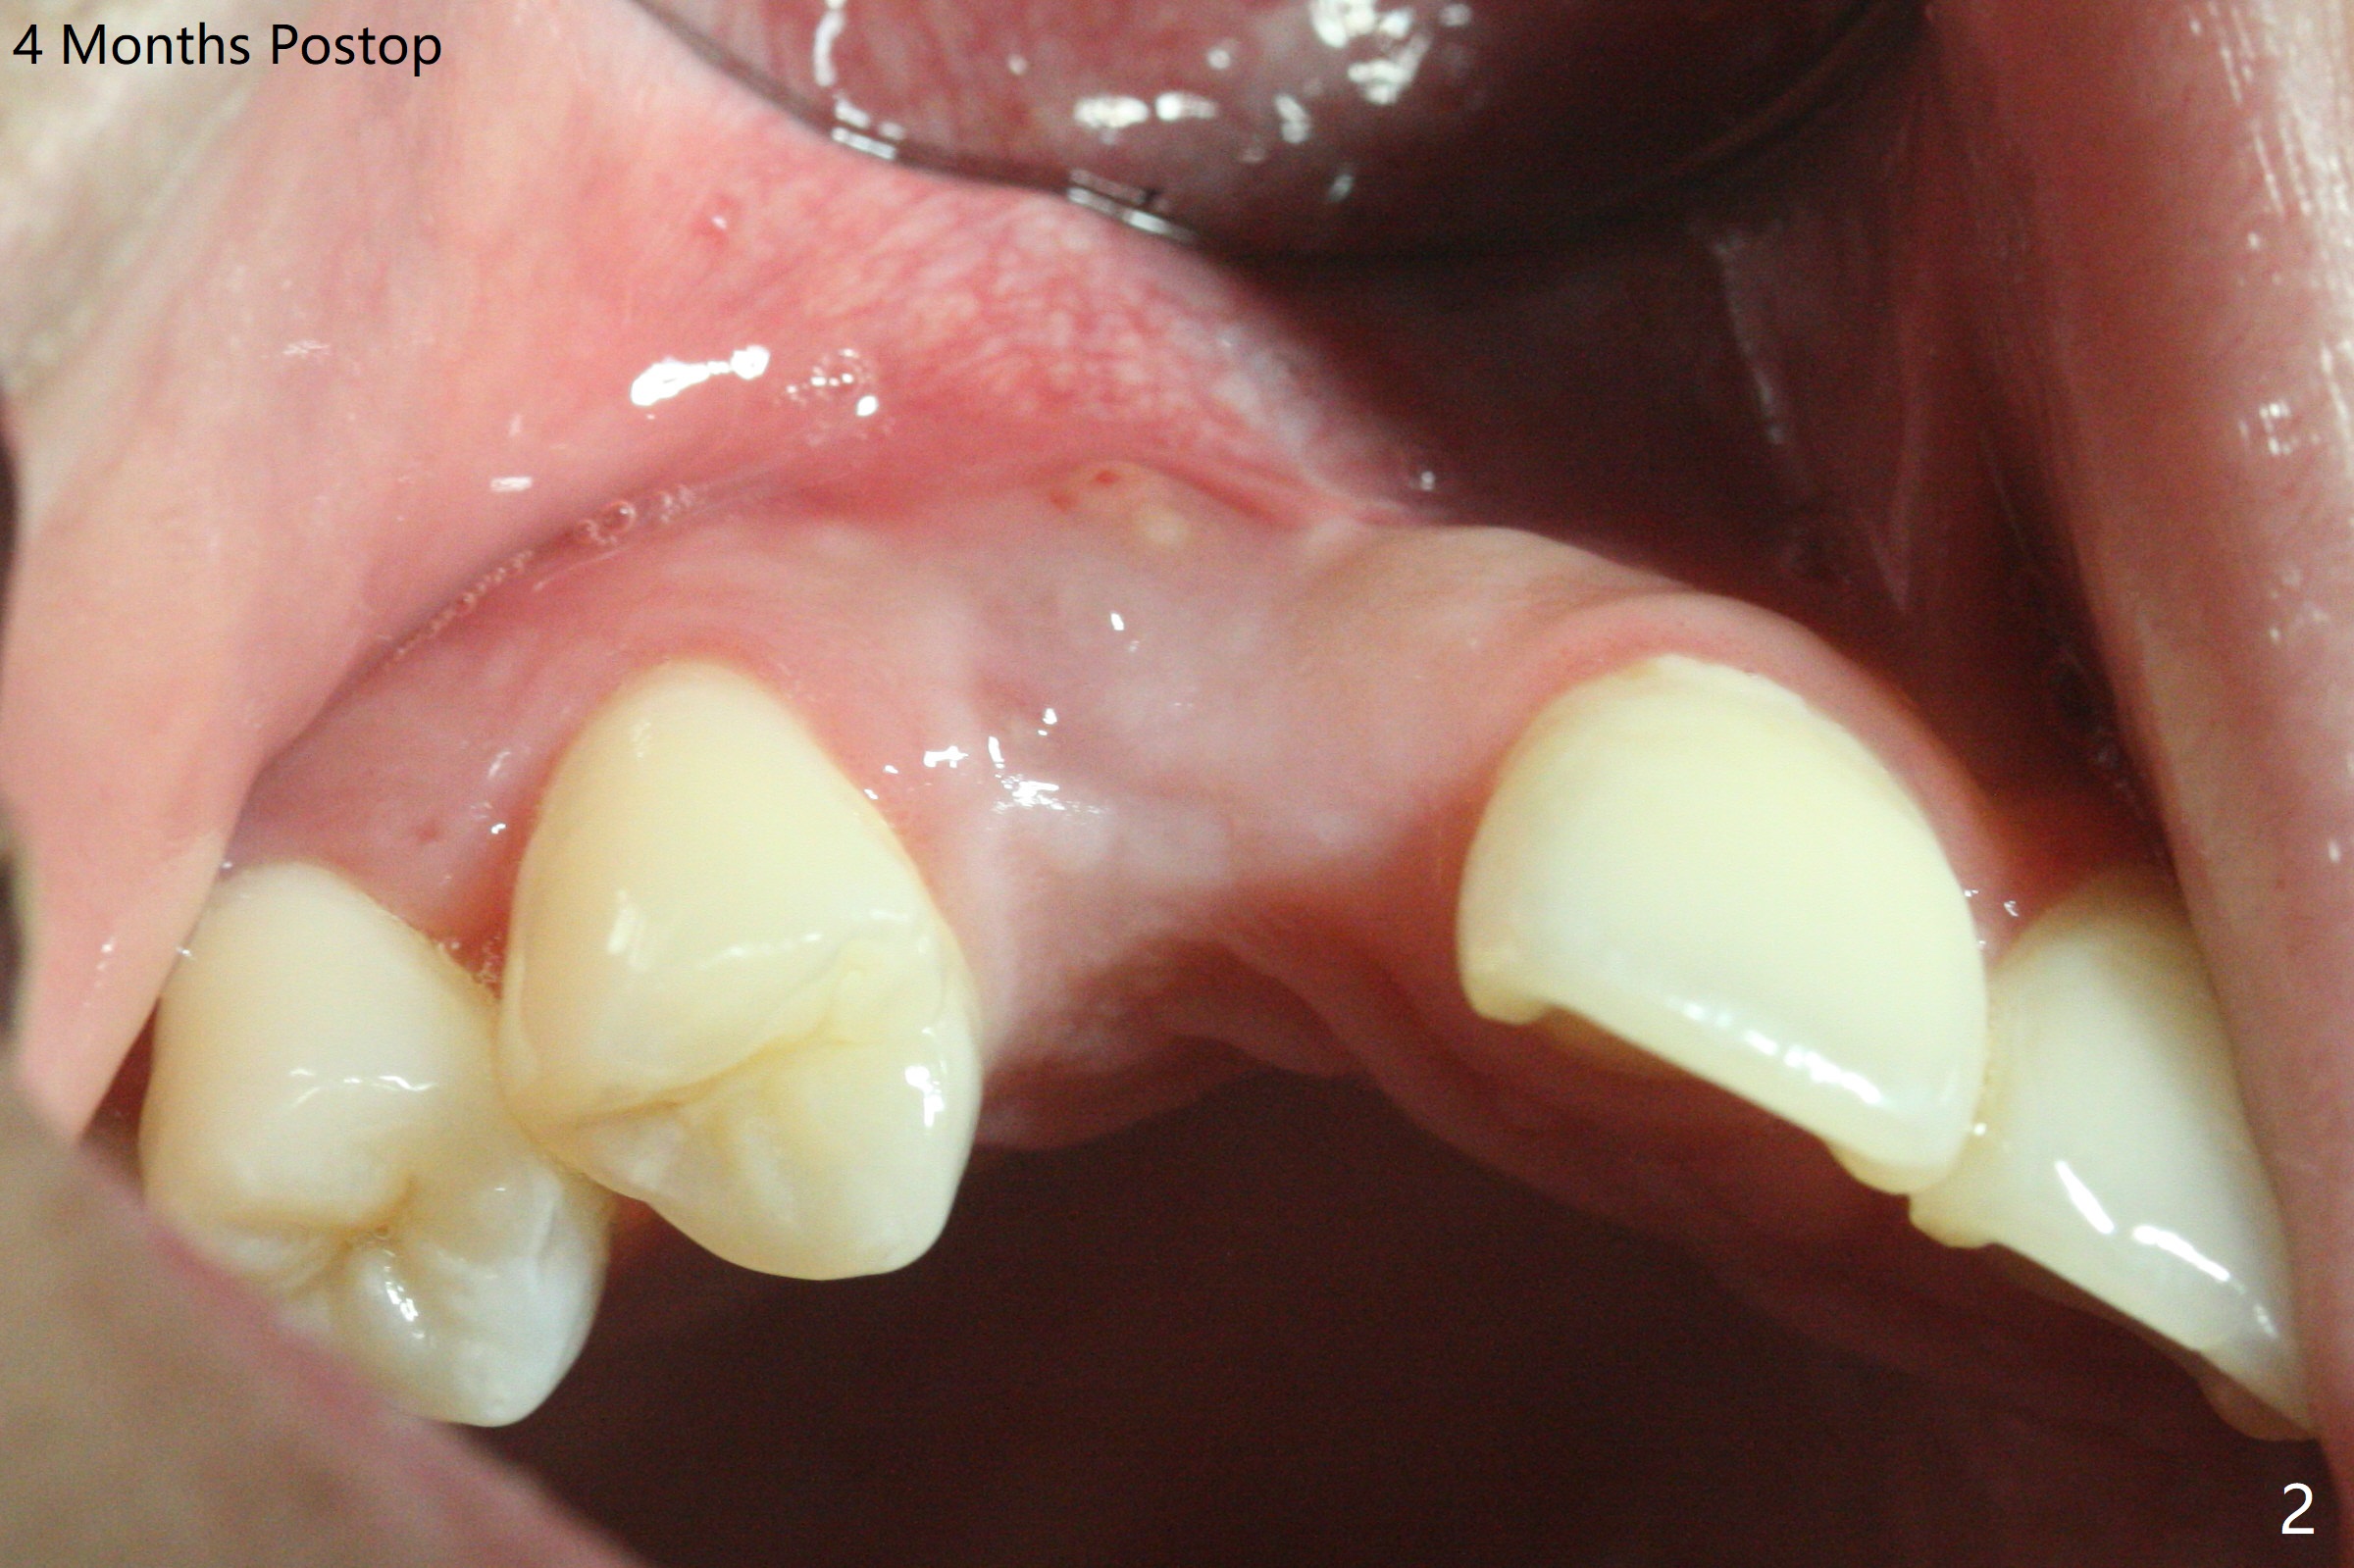

18岁男从外州大学回来,无症状,但是6号牙(右上尖牙)颊侧瘘道(图一,二(角化龈充分(箭头))),根尖片显示植体近中骨吸收(图三:*),而对侧植体仿佛骨整合(图四)。患侧切开后发现植体颊侧暴露,松动。拔除后骨缺损由粘性骨粉修复(图七,九:*),覆盖PRF膜(图七:P)和带钛网(图九:^)不可吸收膜(图五-七),后者用两个小钉子固定(图六(腭侧),七(颊侧),九),使用新的刀片和一个特殊尖头剥离器在颊侧骨膜下相当广泛分离,使用PTFE缝线,粘膜下水平褥式缝合之后(图八:箭头),多个垂直间断缝合,两个乳头垂直褥式缝合。术后一周伤口没有裂开,术后疼痛肿胀已经消退(图十)。术后十八天牙槽嵴仿佛比对侧还要宽(图十一,三与图十二,四(取模)对比)。术后5.5个月伤口没有裂开,牙槽骨,角化龈宽(图十六),与钛网和两个小钉子固定有关(图十五,十七)。CT显示牙槽骨只能容纳2.5或者3.0毫米植体(图十八)。11号牙植体牙冠粘固后没有骨质吸收(图十九),其实10,11号牙颊侧骨板隆起(图二十至二十二),而6植体失败,颊侧骨板吸收,甚至累及5号牙(图十七)。